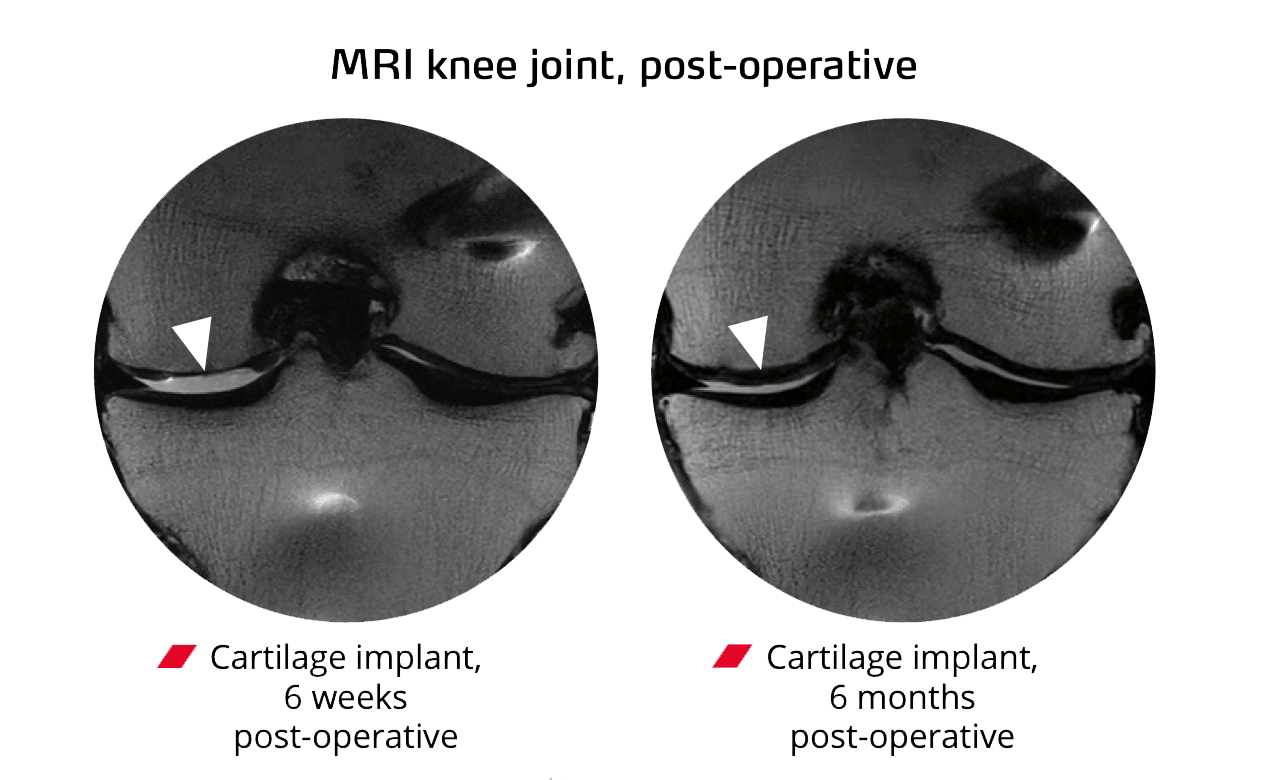

The procedure is short, but the regeneration plays out over months. Here is what happens at each stage.

Over six to twelve months, the body’s own resident cells migrate into the scaffold and lay down hyaline-like cartilage. Improvement typically begins at six to twelve weeks, with continued benefit building over the year.

ChondroFiller is an acellular collagen scaffold that fills a cartilage defect and provides a framework for the body’s own cells to migrate in and regenerate hyaline-like cartilage. Published outcome data shows +30 IKDC in knees, +33 Harris Hip Score in hips, and MOCART MRI scores of 70 to 87 indicating high-quality cartilage regeneration, with over 19,000 global cases supporting safety. Outcomes depend on defect size, location, surrounding cartilage quality and patient suitability.